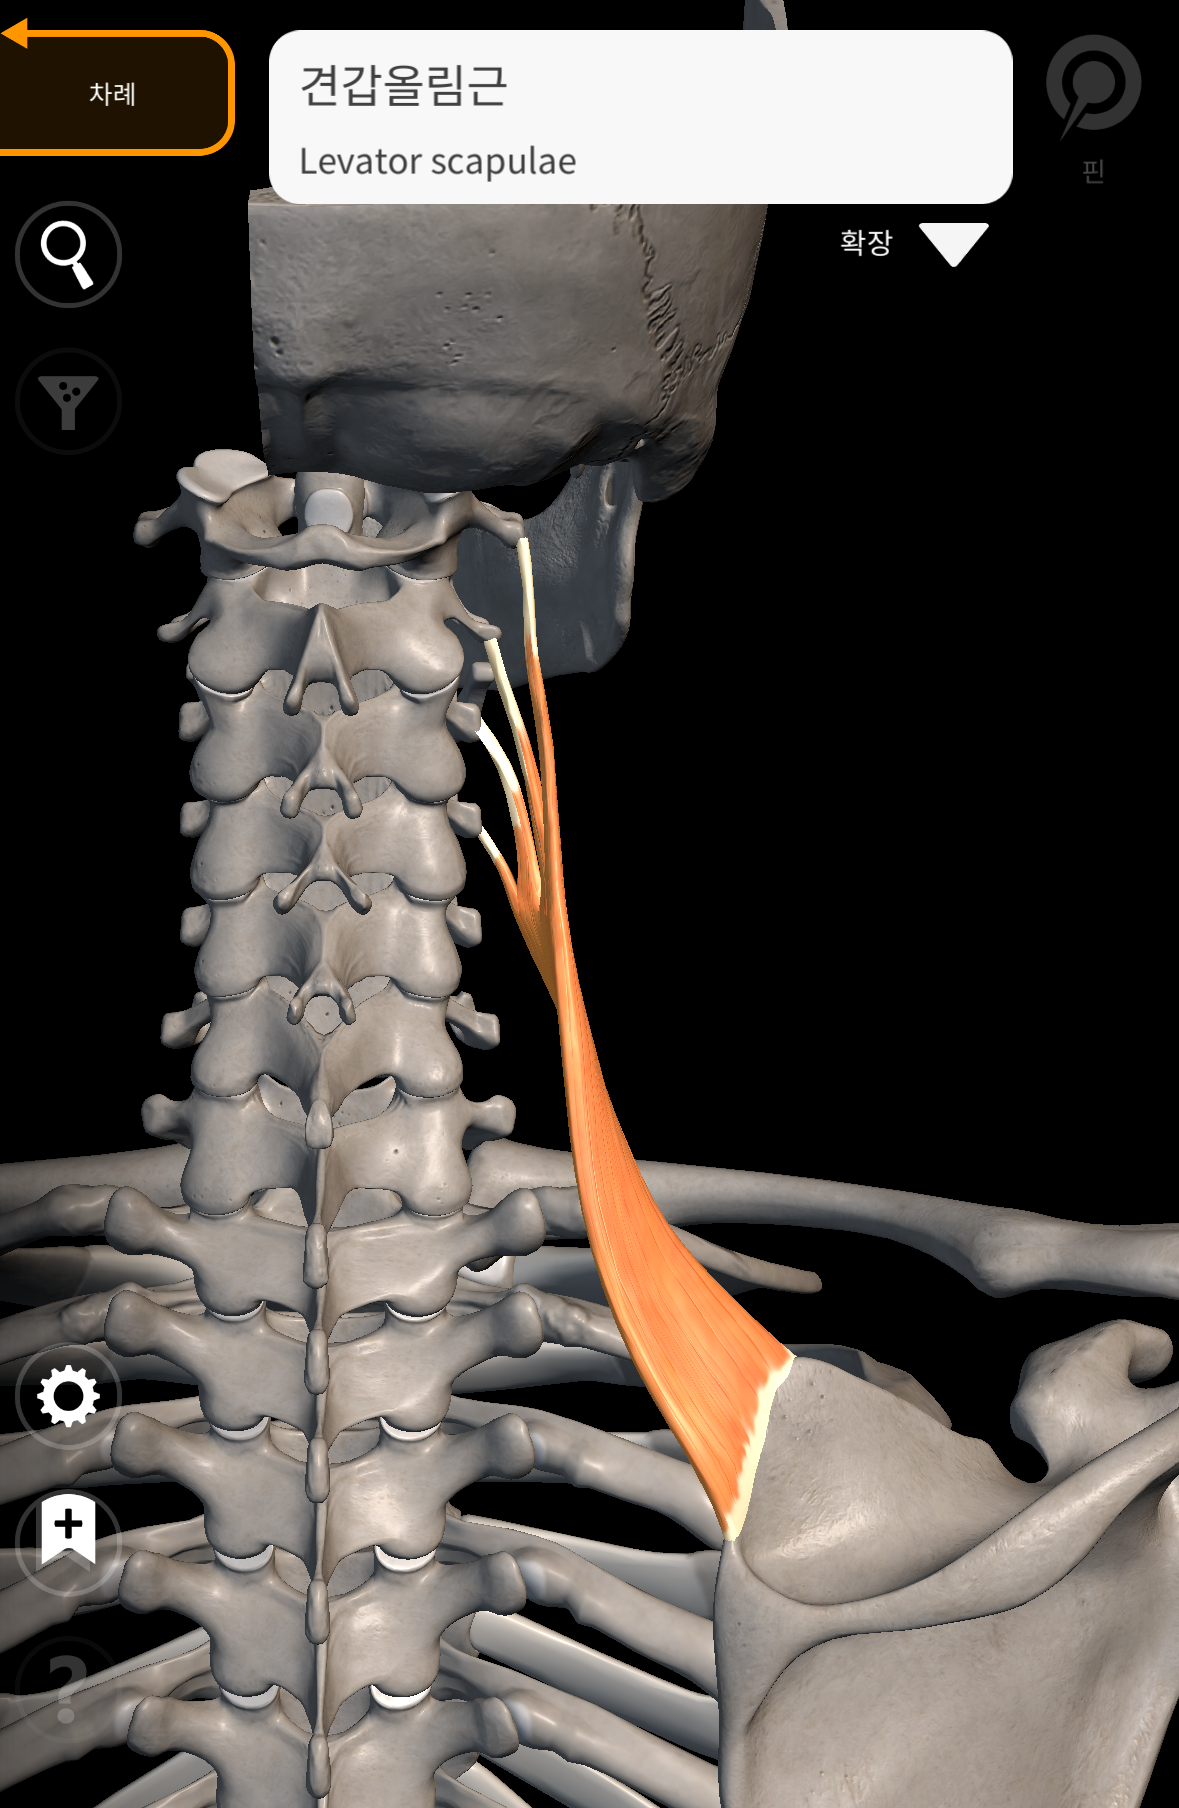

여기서 처진 어깨, 통증의 원인이

대부분 늘어나서 약해진 승모근

때문만이 아닌 '견갑거근'이라는

근육의 문제 입니다. 견갑거근은

날개뼈 외측 상단(위각)에 붙어 경추에

붙는 근육이고, 이 근육의 기능으로는

날개뼈를 하방회전 하는 기능을 합니다.